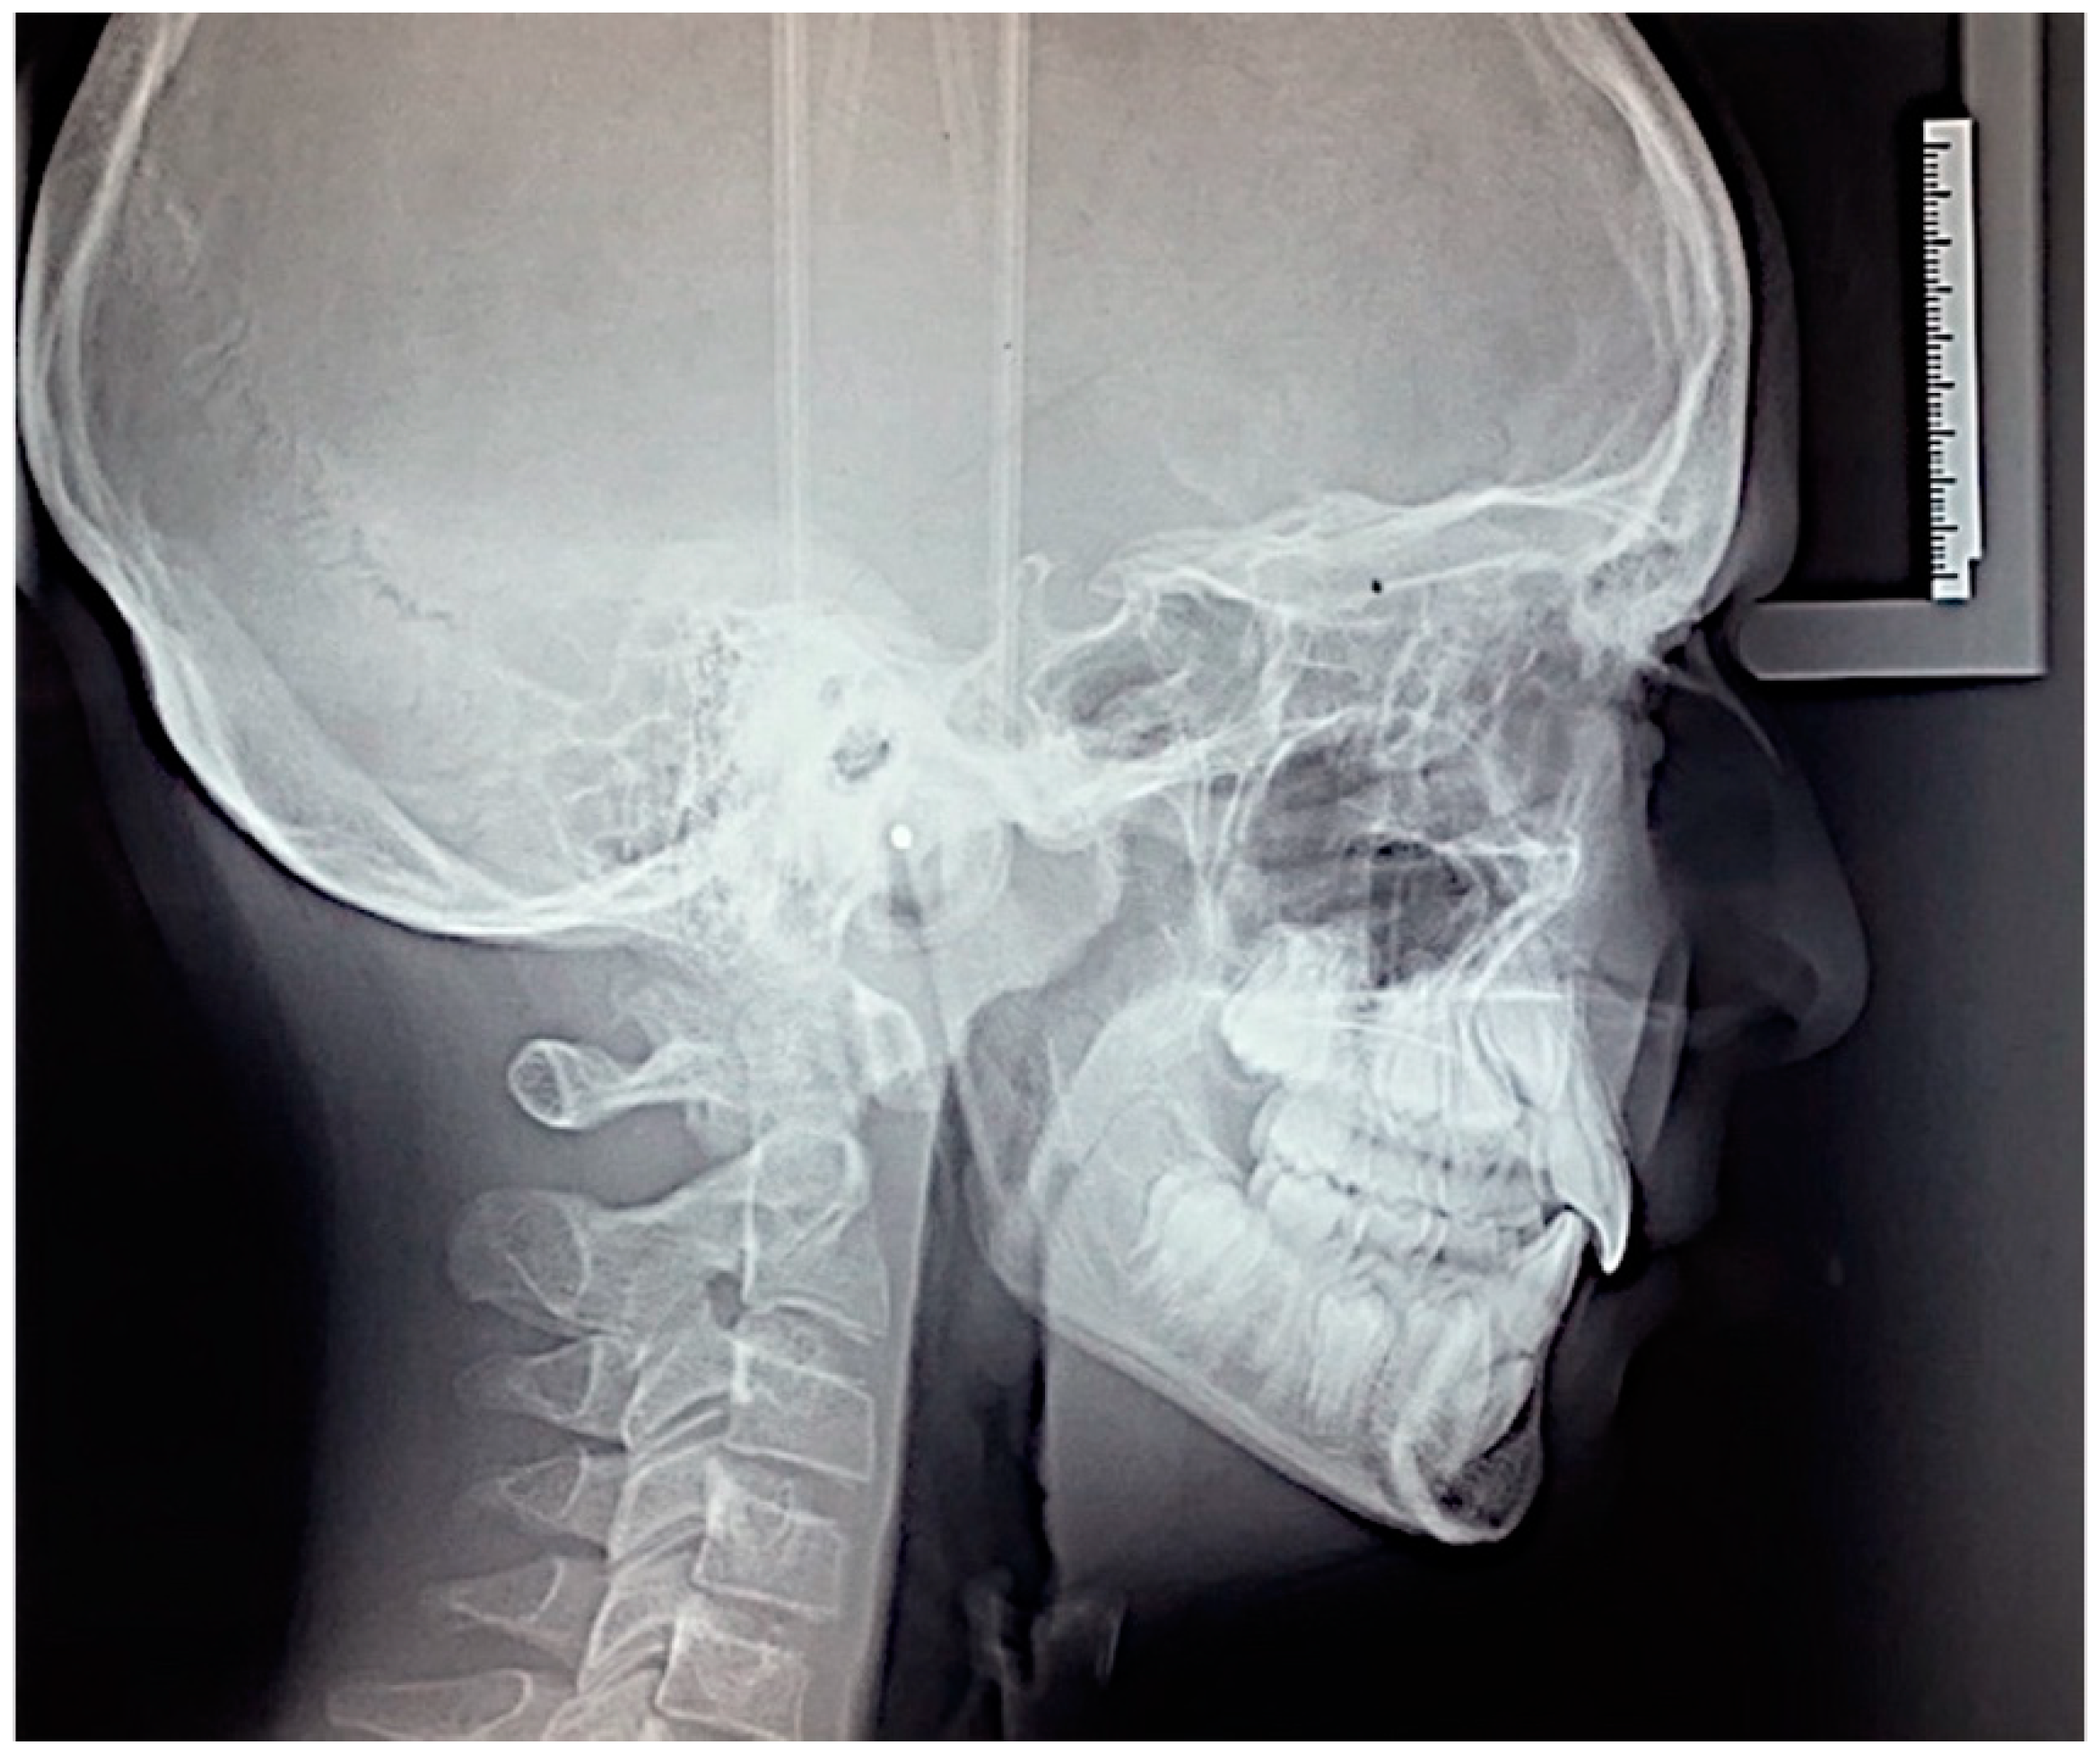

The cephalometric analysis performed using Oris Ceph software Rx CE (Oris Ceph, Elit Computer, Vimodrone, Milan, Italy) showed a skeletal Class I relationship (skeletal class reference angle formed by maxillary point A, nasion and mandibular point B; ANB = 2°) with a hypodivergent vertical grow pattern (angle of divergence from the Frankfurt plane and the mandibular plane, FMA = 21°). The maxillary incisors were palatally inclined (angle of the maxillary incisor inclination with the palatal plane, U1-PP = 102°) and the angle of the mandibular incisors was in in the normal range (angle of inclination of mandibular incisor with mandibular plane, IMPA = 89°) (Figure 4).

Figure 4. Pre-treatment lateral cephalogram.